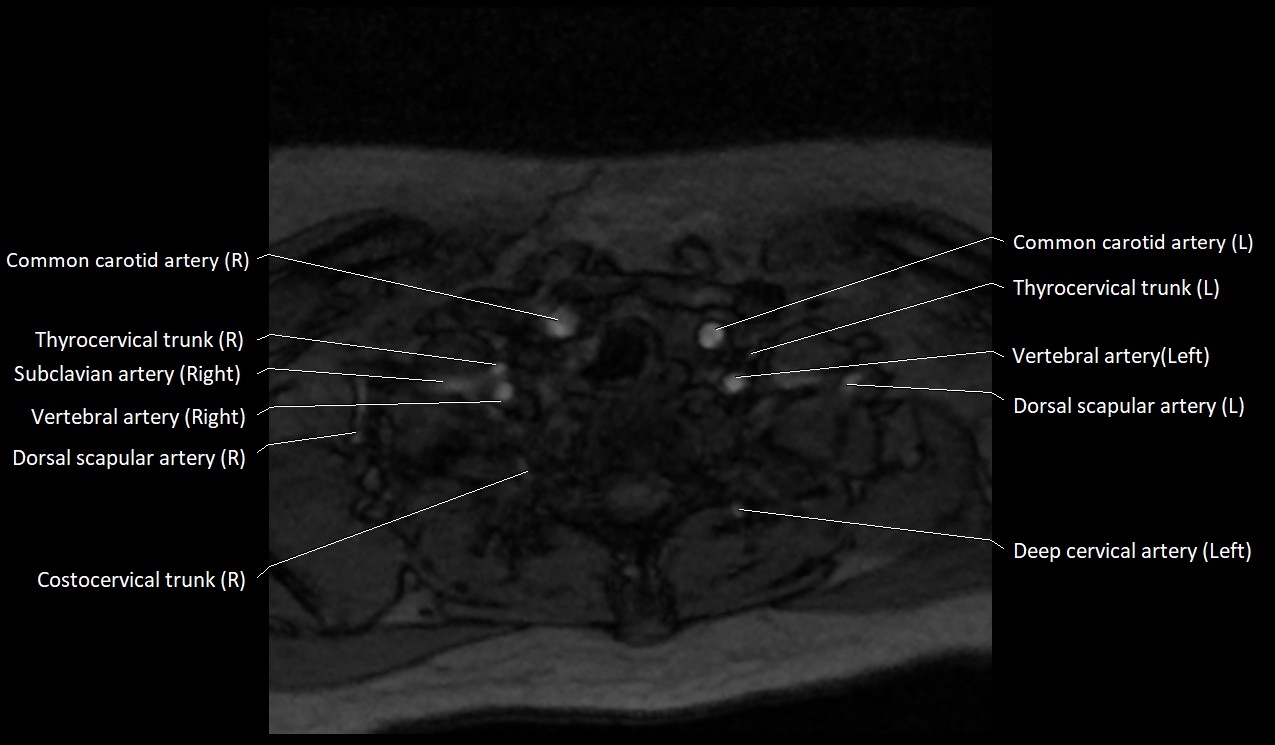

MRI Appearance:

• T1-Weighted Images:

• Appears as a tubular, hypointense (dark) structure relative to muscle

• May show flow void if the blood flow is fast

• T2-Weighted Images:

• Typically hypointense or isointense to muscle, but can be hyperintense if slow flow or stasis is present

MRI images